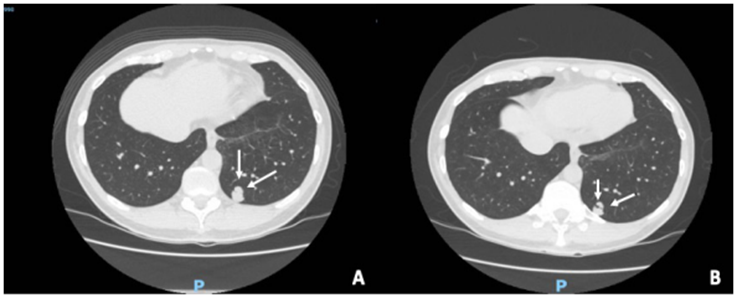

El paciente de la biopsia no conclusiva, que no aceptó una segunda intervención para confirmación histológica, ha tenido aproximadamente dos años de seguimiento radiológico y no ha presentado cambios en la morfología y tamaño del nódulo pulmonar (Figura 1).